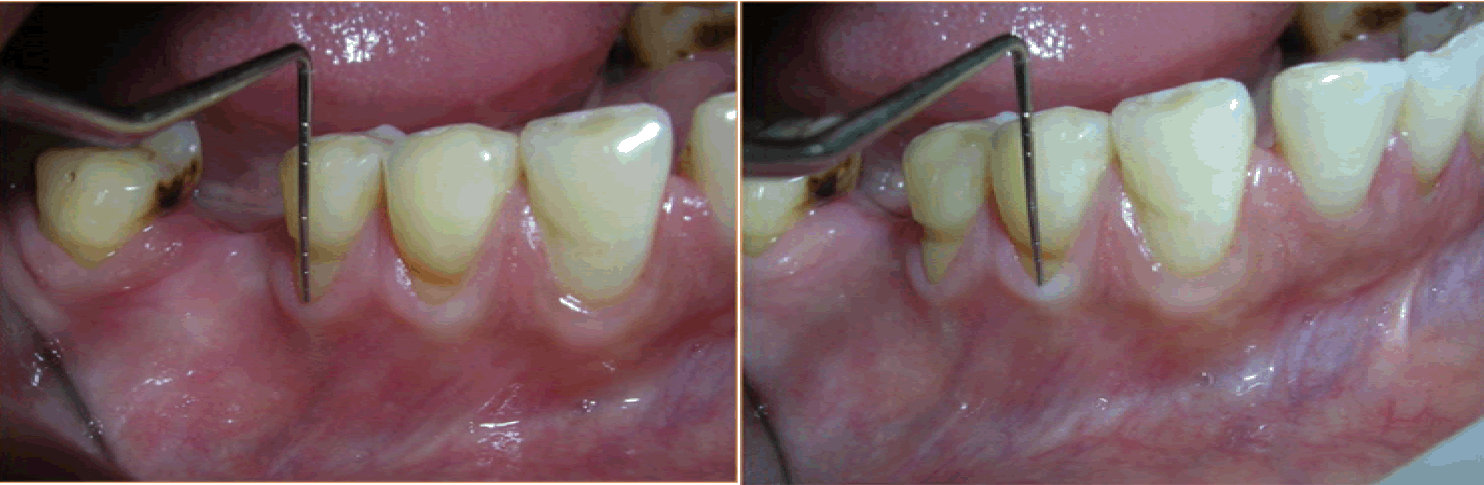

Case 2: A 31-year-old male presented with the chief complaint of sensitivity in the lower teeth and was clinically diagnosed as a case of Millers Class II recession in relation to 33 and 34 (Figure 5). The same surgical technique, as in Case 1, was used to place the connective tissue graft in the pouch created in relation to 33 and 34.

Figure 5: Millers Class II recession in relation to 33 and 34.

Figure 8: Postoperative image after 18 months (Case 2).